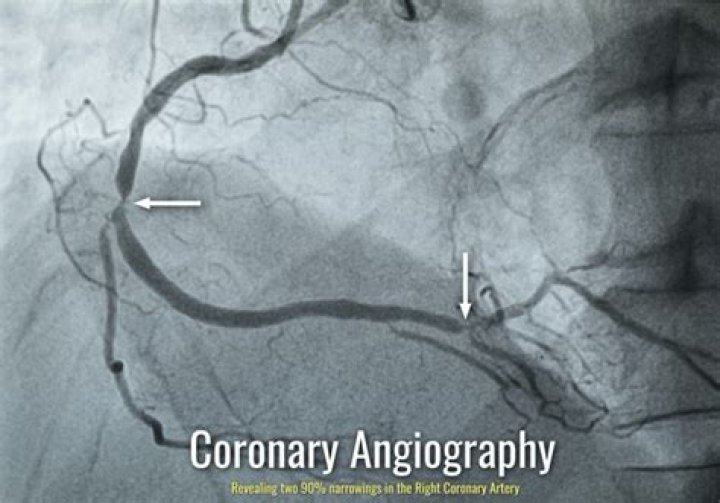

A health care provider uses the angiogram to check for blocked or narrowed blood vessels in your heart. A coronary angiogram is a procedure that uses X-ray imaging to see your heart’s blood vessels. The test is generally done to see if there’s a restriction in blood flow going to the heart.

Long-term outlook after a coronary angiogram Narrowed coronary arteries may possibly be treated during the angiogram by a technique known as angioplasty. A special catheter is threaded through the blood vessels and into the coronary arteries to remove the blockage.